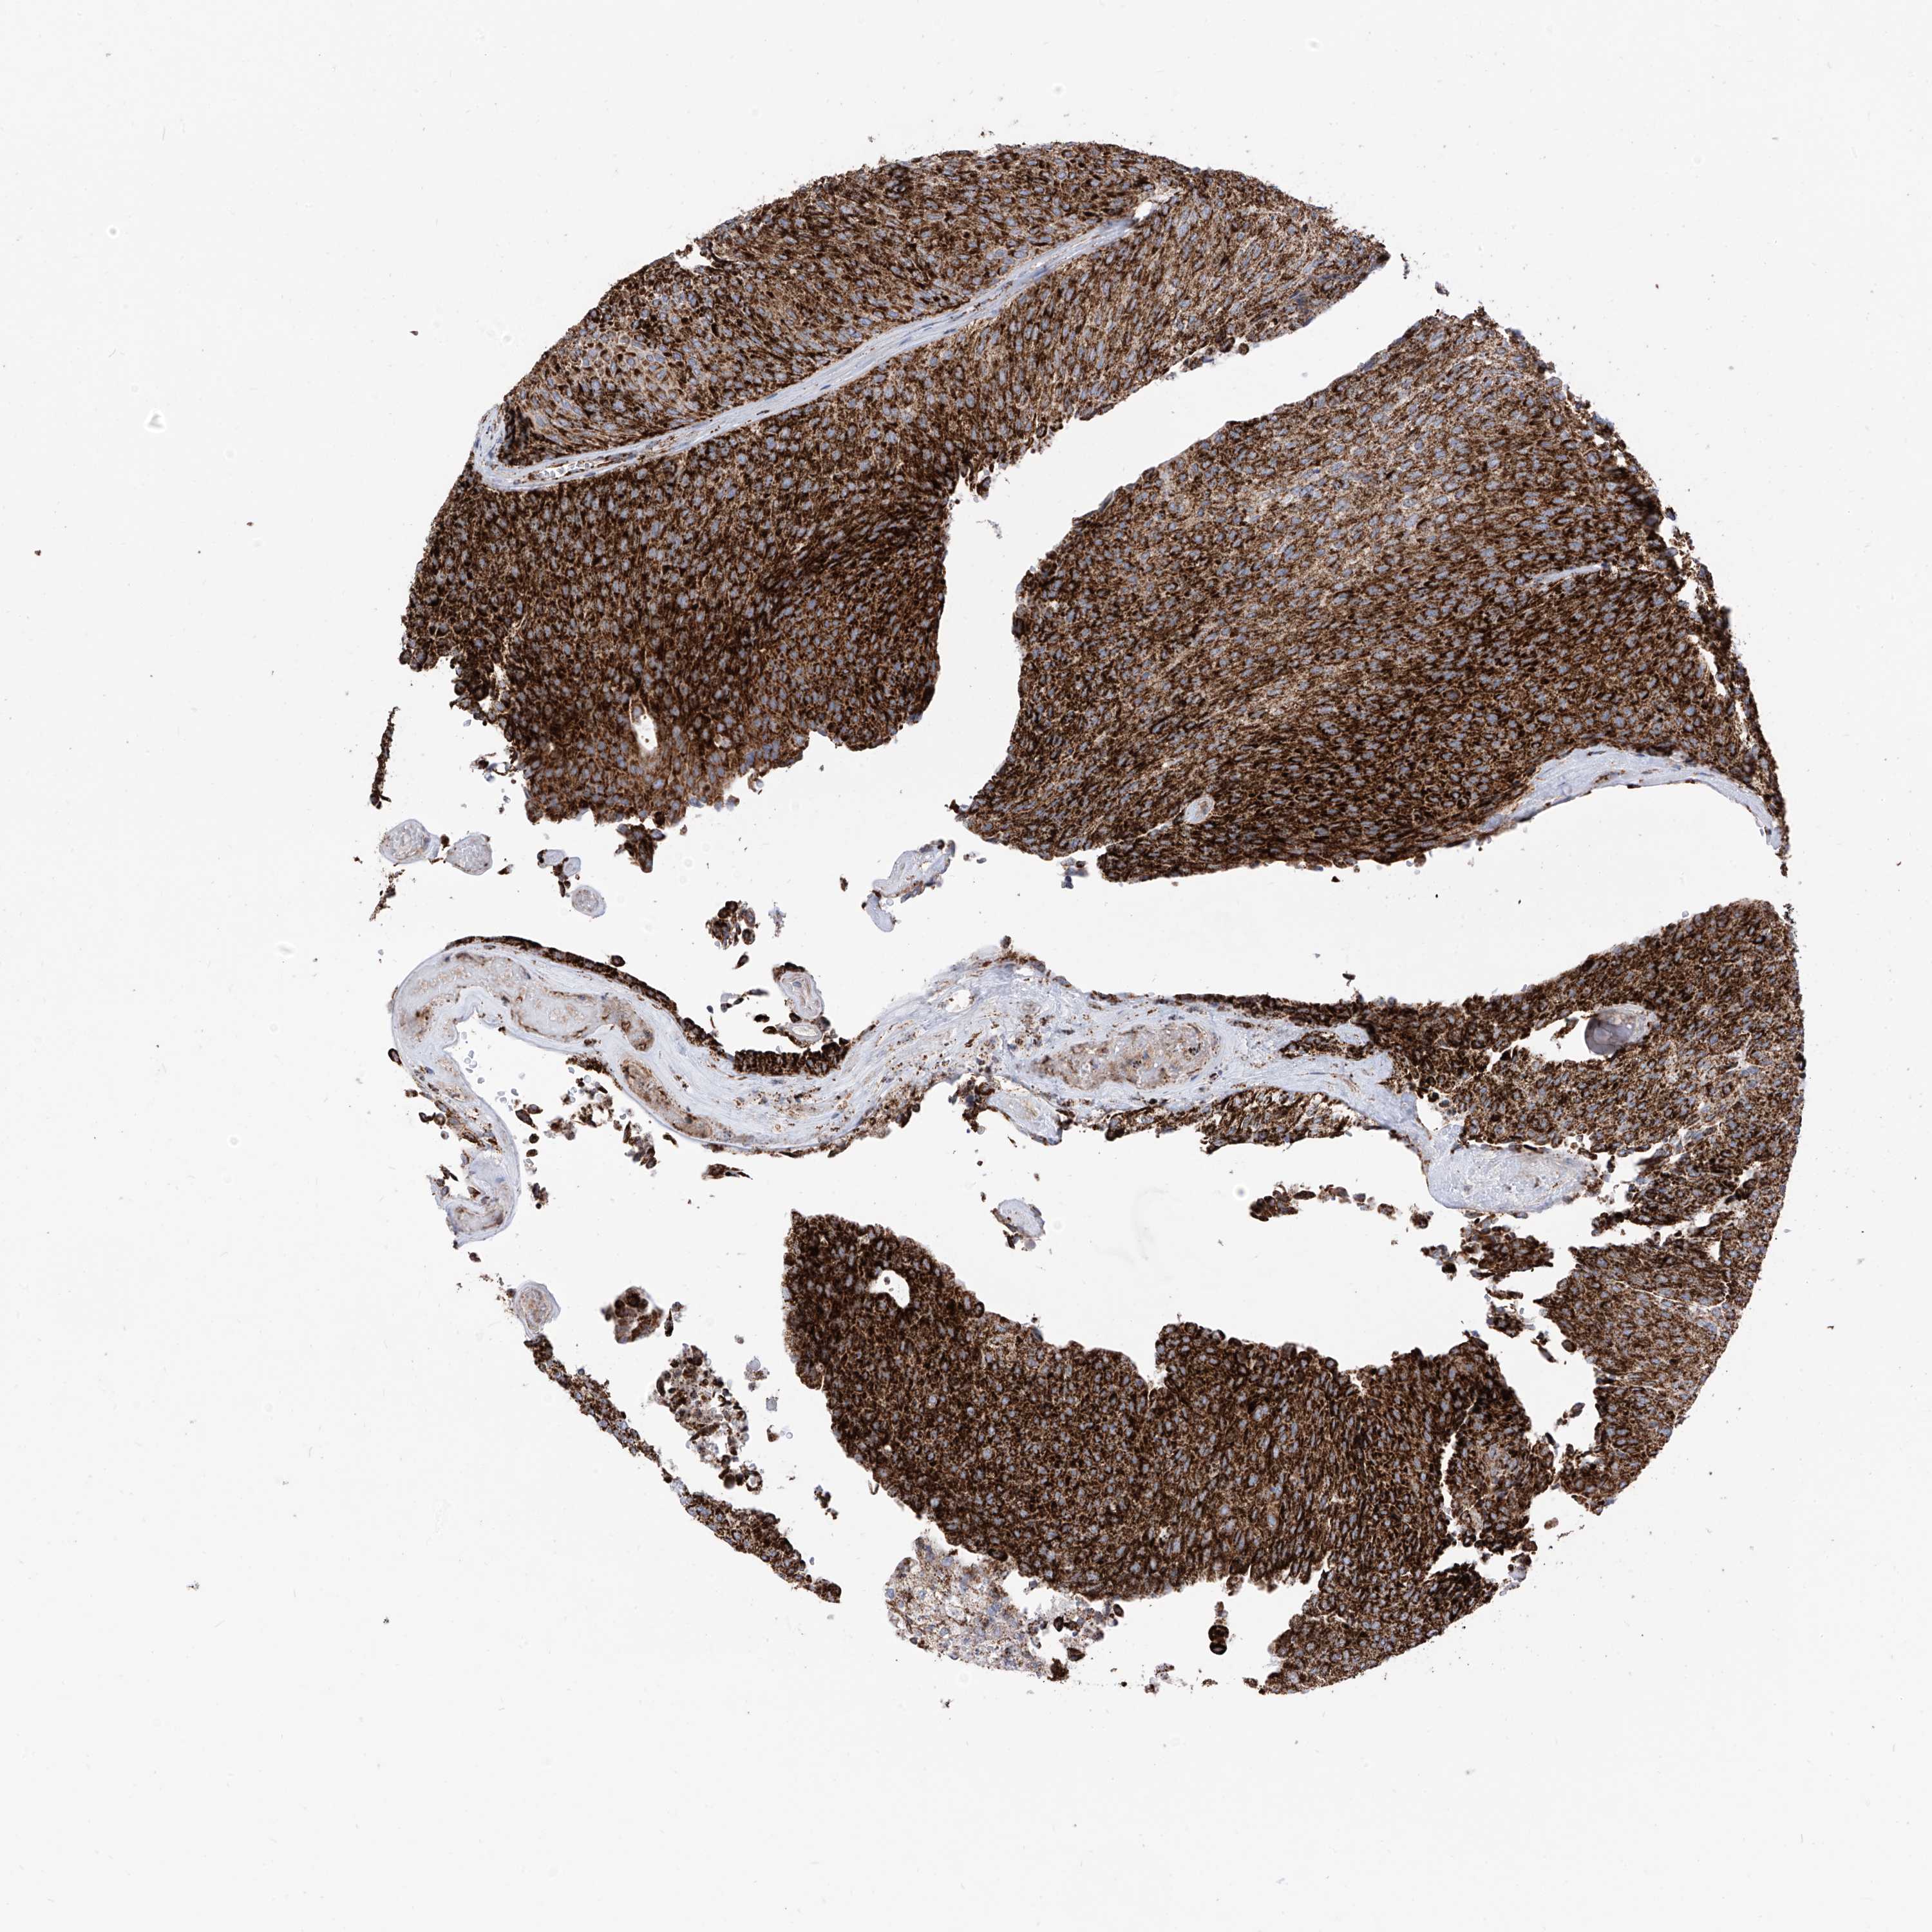

UROTHELIAL CANCER - Protein expressioni

A mouse-over function shows sample information and annotation data. Click on an image to view it in a full screen mode. Samples can be filtered based on level of antibody staining by selecting one or several of the following categories: high, medium, low and not detected. The assay and annotation is described here.

Note that samples used for immunohistochemistry by the Human Protein Atlas do not correspond to samples in the TCGA dataset.

Antibody stainingi

Antibody staining in the annotated cell types in the current human tissue is reported as not detected, low, medium, or high, based on conventional immunohistochemistry profiling in selected tissues. This score is based on the combination of the staining intensity and fraction of stained cells.

Each image is clickable and will lead to virtual microscopy that enables deeper exploration of all samples and also displays staining intensity scores, fraction scores and subcellular localization as well as patient and tissue information for each sample.

Antibody HPA034517

Staining

High

Medium

Low

Not detected

Intensity

Strong

Moderate

Weak

Negative

Quantity

>75%

75%-25%

<25%

None

Location

Nuclear

Cytoplasmic/membranous

Cytoplasmic/membranous,nuclear

Urothelial carcinoma, Low grade

Urothelial carcinoma, High grade